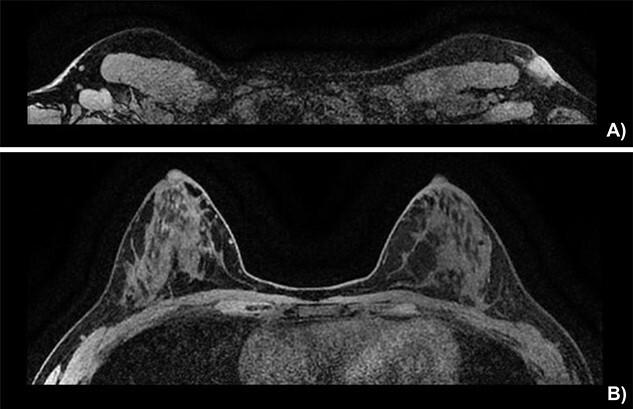

Locally advanced breast cancer arising in the axilla.

Locally advanced breast cancer arising from ectopic axillary breast tissue is an unusual presentation of this malignancy. The work-up and treatment approach pose some unique challenges. We present the case of a 37-year-old female presenting with a left axillary lesion with skin involvement. Radiological studies and biopsy demonstrated an underlying axillary mass compatible with a triple-positive invasive ductal carcinoma of the breast. Following neoadjuvant therapy, the patient underwent nipple-sparing mastectomy with wide local excision of the involved axillary skin and axillary lymph node dissection. Ectopic locally advanced breast cancer can be treated similarly to its orthotopic counterpart, favoring a neoadjuvant therapy approach followed by surgical excision. Special considerations include the local anatomy of the tumor, the extent of surgery and reconstructive options.